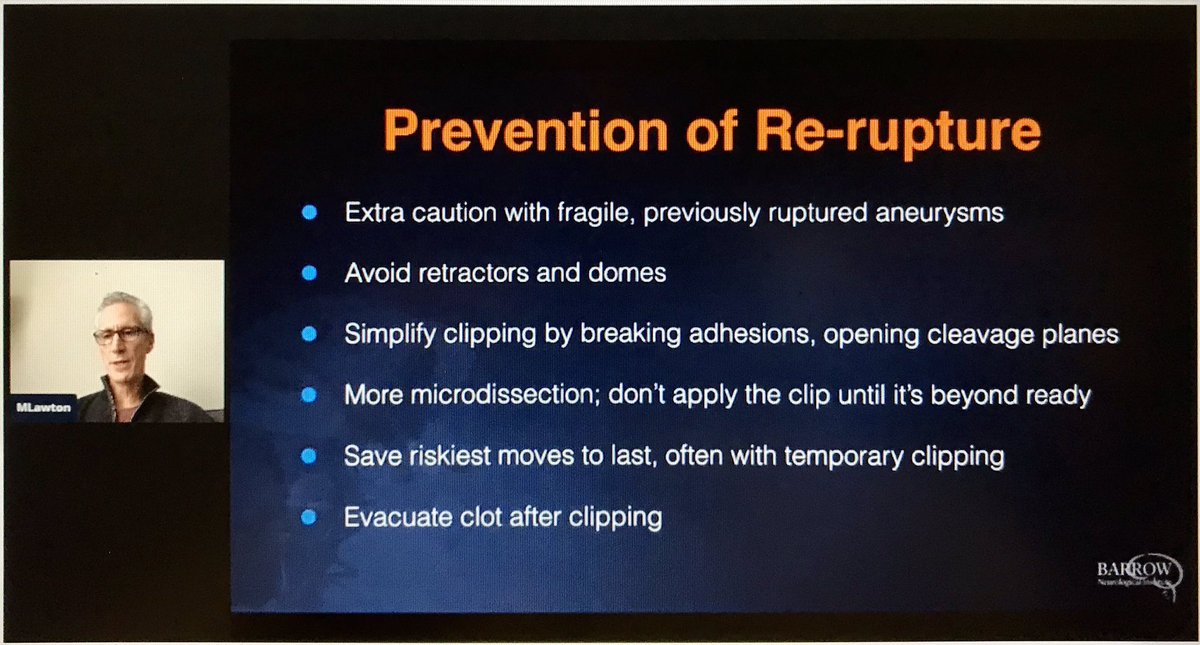

In today’s podcast we‘re joined by Michael T. Lawton, MD, chair of #neurosurgery at BarrowNeurological, as he shares what it takes to become a master surgeon - passion, innate skill, and work ethic - and lessons learned from watching Robert Spetzler during his training podcasts.apple.com/us/podcast/neu…